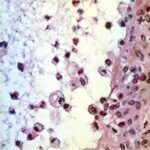

Atlas of skin histopathology

Mucus Retention =الأحتباس المخاطي